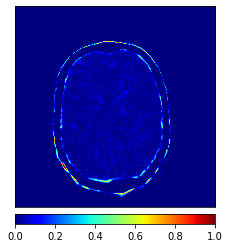

In addition, we have conducted an experiment to show the sensitivity of DC-cycleGAN to . To achieve this, is varied from 0.1 to 1. As shown in Fig. 8, the DC-cycleGAN produces the best results for both directions when is set to 0.5.